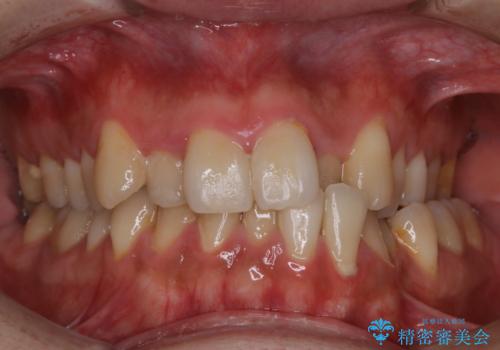

- 忙しく歯科医院でのメンテナンスが1年ぶりとのことで来院されました。PMTC60分コースを行いました。

PMTCを定期的に行い、お口の中を清潔に保つことで長期的に健康なお口の状態でいられることにつながりなす。

毎日かかさず食べる・飲む・噛む・話すなど当たり前の日常生活を快適に送れるように、歯科衛生士による専門的なクリーニングでサポートさせていただきたいと思います。